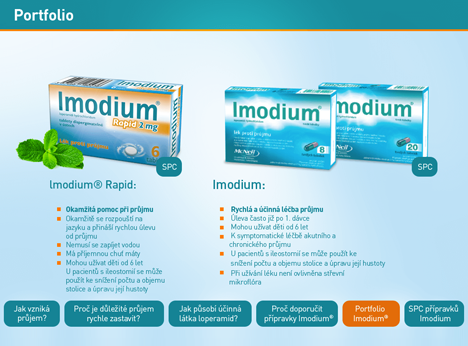

- Corporate design

- Co komunikuje s vašimi klienty, pokud to nejste vy osobně? Je to corporate design (nepřesně zjednodušován pojmem logo). Kvalitní corporate design je důkazem vyspělé firemní kultury. Klient vás díky němu neomylně identifikuje a to i díky mobilní aplikaci, která musí CI respektovat.